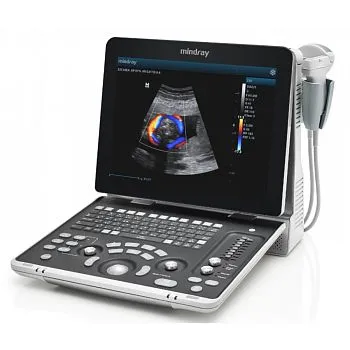

УЗИ аппарат Mindray Z60 портативный

Клинические изображения

Аппарат УЗИ Mindray Z60 является новой, переосмысленной версией популярного сканера Mindray DP-50. Аппарат оснащен двумя портами для подключения датчиков и опционально может иметь дополнительный третий порт. Система поддерживает такие продвинутые технологии как компрессионная эластография, а так же 3D/4D исследование и может быть укомплектован более современными датчиками.

Основные преимущества новой системы заключаются в компактном дизайне, возможности регулировки угла наклона монитора до 60 градусов, 15” экран с антибликовым покрытием, жесткий диск 1Т, батарея на 1,5 часа автономной работы, до 3-х встроенных портов для датчиков.